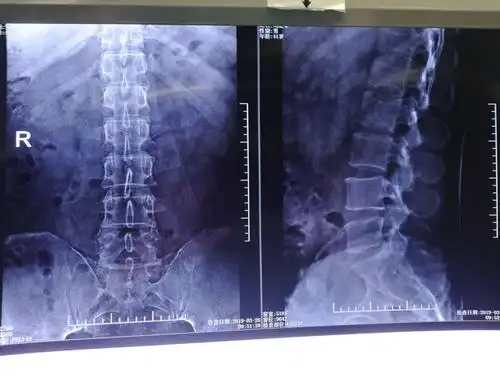

病人术前片子,腰五骶一椎间盘突出.

腰间盘突出片子怎么看

腰椎间盘突出的影像诊断

男.52岁 典型腰椎间盘突出症病例

旁中央型腰间盘突出症病人.39岁女性病人

腰椎间盘突出症的影像学检查